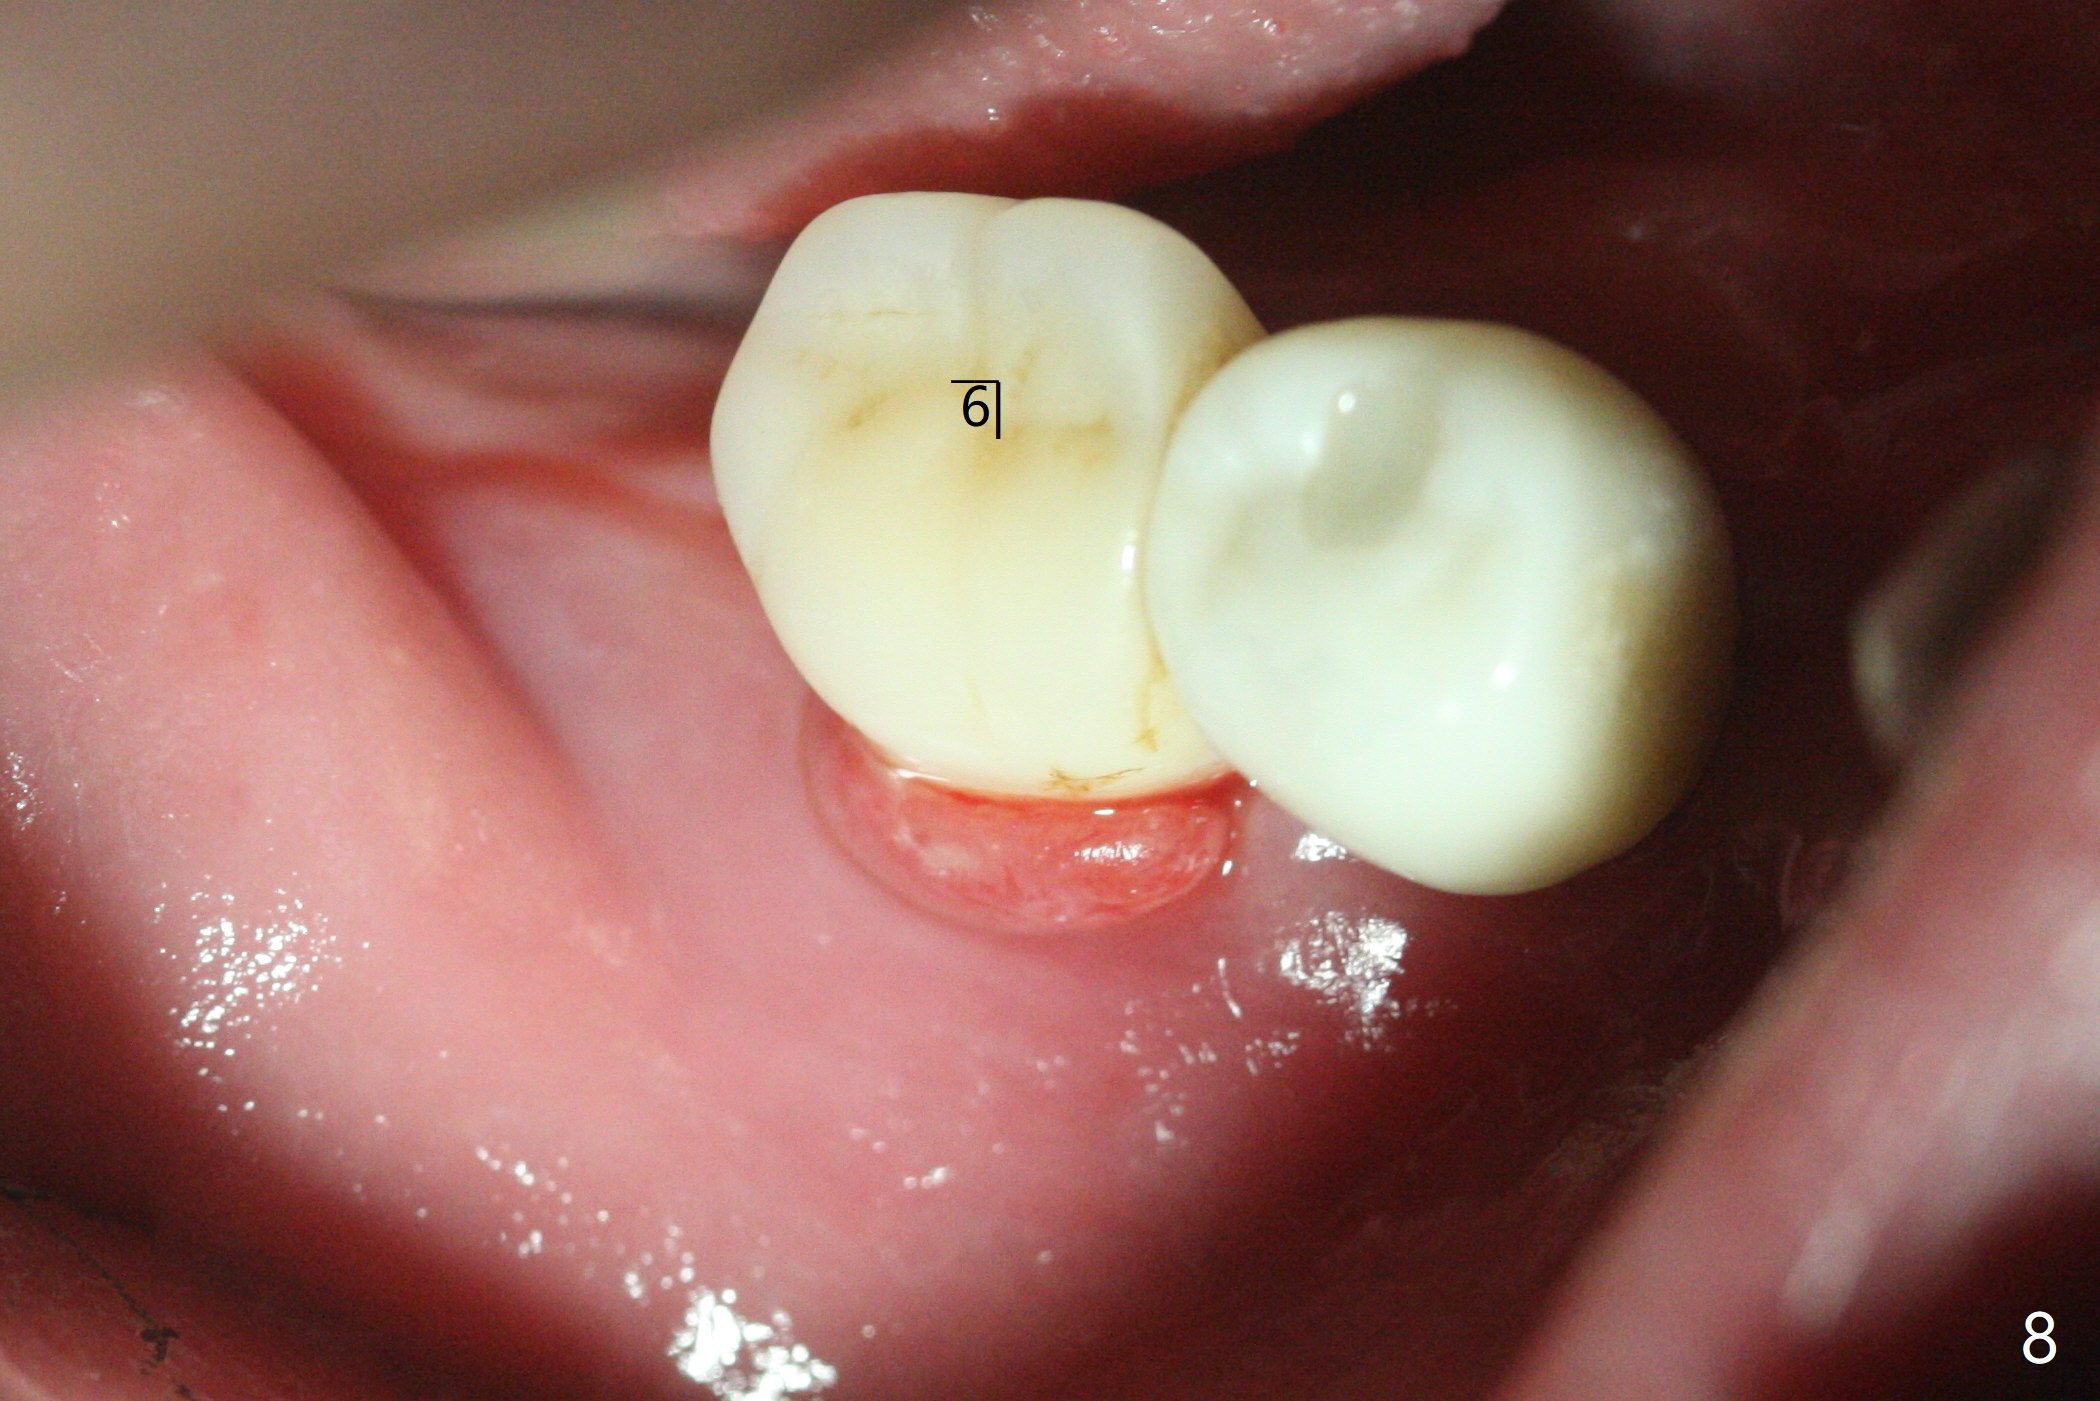

52岁男右下4植体脱落三天回到诊所(图一),植牙创尚未闭锁,顺着开口去除肉芽组织,冲洗,充填皮质骨骨粉(图二,三),颊侧骨板外形恢复(图四,五:*)。重新植入UF植体(5)颊侧还有薄颊侧骨板(图五:>),而6植体周围骨质吸收(图六),植骨好像有希望,植体还在牙槽骨范围,也有利于5植体生存。术后12天伤口愈合(图七)。尽管使用水枪,仍有6植体周围炎,需要治疗(图八)。由于右侧手术,病人不得不用左侧咀嚼,他认为左下4松动,无法挽救。术后3.5个月牙槽嵴和角化龈缩小(图九),需要切开使用导板。术后3.5个月骨粉高度明显下降(图十)。只能植入4x8.5毫米植体(图十一)。